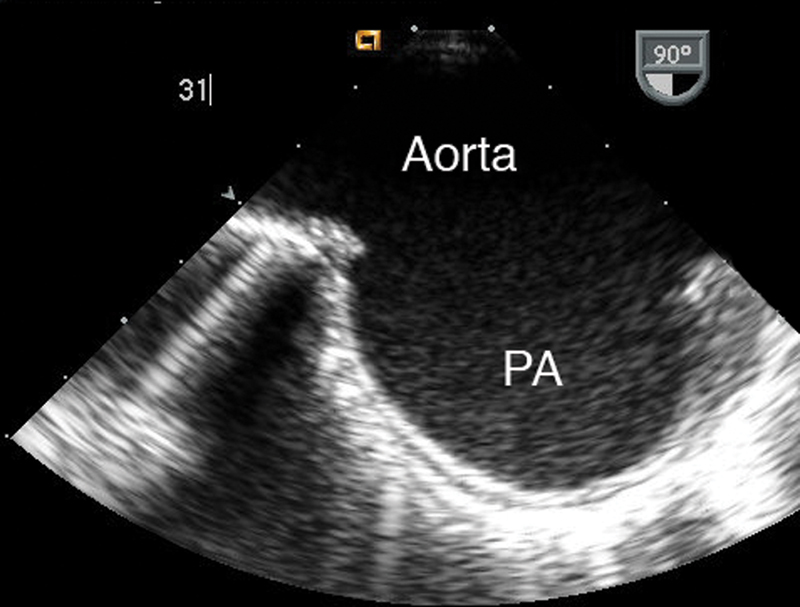

فحوصات تشخيصية لبعض امراض القلب والشرايين التاجية